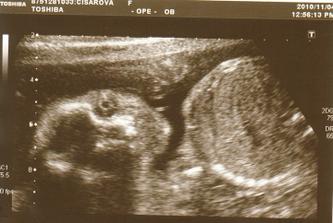

4.11. Velký UTZ v Motole. Čekáme holčičku!!! Všechno je v pořádku. Máme 465g a malá byla opravdu čiloušek.

23.11. 3D UTZ na poliklinice Škodovky v Mladé Boleslavi. Byl to úžasný zážitek. Malá se hezky ukázala, má 681g. Všechny míry jsou v normě. Už víme, že nosík má po mamince a bradičku po tatínkovi🙂